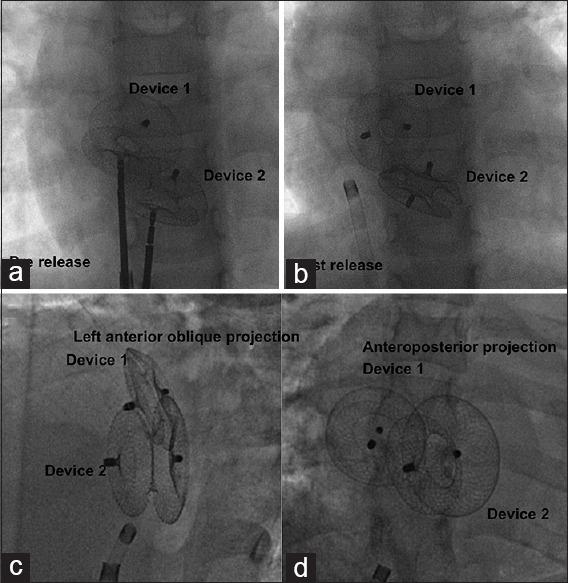

Patients who received multiple devices for closure of MASD were grouped according to their age and analyzed for procedural techniques, immediate and late complications. MASDs closed by a single device were not included. Balloon sizing was done when echocardiographic images were suboptimal before simultaneous device deployment through two venous accesses or sequential deployment through one access. Duration and number of antiplatelet drugs and residual flows were analyzed on follow-up.

Twenty-five patients received multiple devices. Balloon interrogation was performed in 16/18 adults but only in 2/7 children. Device size was 2-5 mm larger than echocardiographic defect size or equal to balloon waist. There were no procedural failures; 7/25 showed small postprocedural residual flows. Complications including embolization in one, arrhythmia in one, and cobra deformity in two were managed successfully. On a median follow-up of 5.5 years (1-12 years), residual flows disappeared in 4/7 and there were no major late complications.

Use of multiple devices for closing MASD is feasible with good technical success. Echocardiography and balloon interrogation are the keys for success. Simultaneous deployment is often needed and sequential delivery is feasible rarely if the defects are far apart. Minor residual leaks are common but improve on follow-up. There are no significant new complications on long-term follow-up.